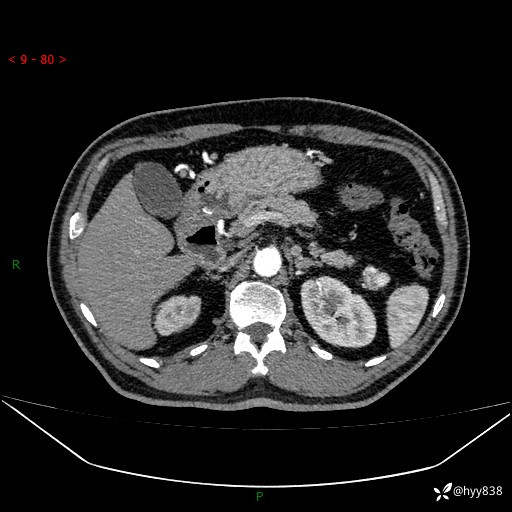

讨论:病变性质?

静脉期